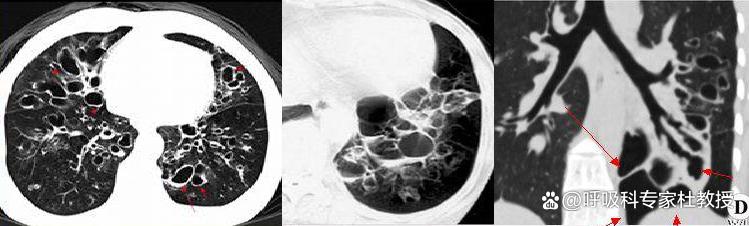

三、静脉曲张征:因支气管壁遭到严重破坏,边缘凹凸,各段支气管扩张程度不同,变现出类似静脉曲张或串珠状,是静脉曲张型支扩的典型表现。

四、蜂窝征:扩张的支气管呈囊袋装,如葡萄一样成团出现,像蜂窝一样,囊内可因有液体存在而出现气液平面。